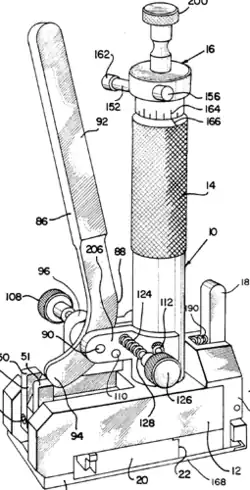

| Trocar |

|

Access instrument. Used to create an opening into a space without opening the abdominal cavity. A camera is inserted through one to view the interior while instruments are inserted through the others to manipulate the organs. | |